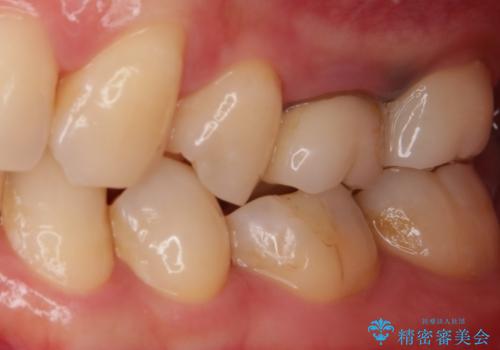

インプラント治療により、周りの歯を削ることなく咬合を回復することができました。